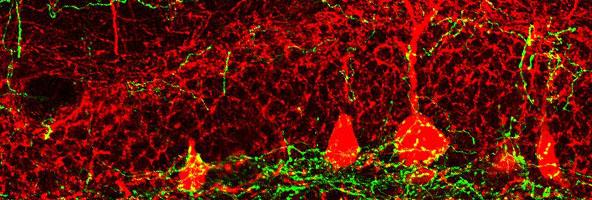

Reported as the cover story in Cell Stem Cell , the researchers identified a neurogenesis-controlling brain circuit that runs from near the front of the brain back to the hippocampus, a learning- and memory-related structure. The hippocampus is one of the major sites of neurogenesis in the adult human brain, and the circuit that Song's team has identified regulates this neuron-producing process.

The chief exception is the dentate gyrus (DG) region of the hippocampus. Neurogenesis in the DG occurs throughout adult life and supports the hippocampus's crucial functions in storing and retrieving memories. DG neurogenesis has been linked to mood as well. In fact, scientists suspect that the mood-improving effects of antidepressant drugs and physical exercise arise at least in part from the boost they give to DG neurogenesis.

How the brain controls DG neurogenesis, dialing it up and down when needed, is a mystery that Song and her team have been trying to solve since Song started her lab at UNC in 2013. In a study published in the journal Nature Neuroscience, for example, they found that special local hippocampal neurons called PV interneurons provide signals to DG newborn progeny that appear to be crucial for healthy neurogenesis.

In the new study, Song and colleagues discovered that this hippocampal PV interneuron-signaling is regulated by a GABA circuit coming from the medial septum, a cluster of neurons near the front of the brain.

"This medial septum GABA circuit works through the local PV interneurons in the hippocampus to instruct stem cells to become activated or to stay quiet," Song said. "This GABA circuit is unique, because local PV interneurons are excited by GABA, a brain neurotransmitter that normally inhibits neuronal activity."